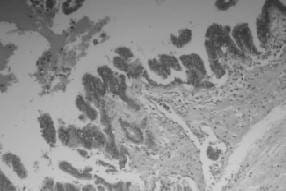

La presencia de mucina no especifica el grado patológico del tumor y que sea negativa no excluye la presencia de neoplasia intraductal mucinosa de páncreas; las células epiteliales de uniones fuertes están asociadas a neoplasias con displasia moderada y, las células inflamatorias y la paracromatina, con el carcinoma in situ. La necrosis está asociada a la invasión (4) (figura 3).

Estudio Histopatológico de Páncreas Utilizando Coloraciones de Hematoxilina Eosina

FIGURA 3. Estudio histopatológico de páncreas utilizando coloraciones de hematoxilina eosina. Dilatación del conducto pancreático principal, neoplasia intraductal mucinosa con células epiteliales con atipia 10X.